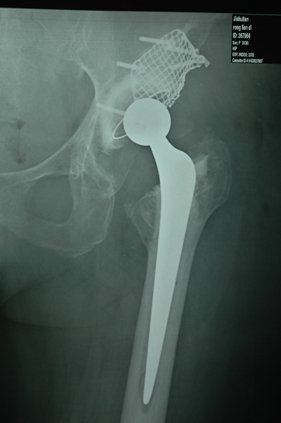

Department of Adult Joint Reconstructive Surgery

rivision total hip replacement for dislocation and severe bone defect

(post-op)rivision total hip replacement for dislocation and severe bone defect

lateral view of left hip

anterior-posterior view of left hip